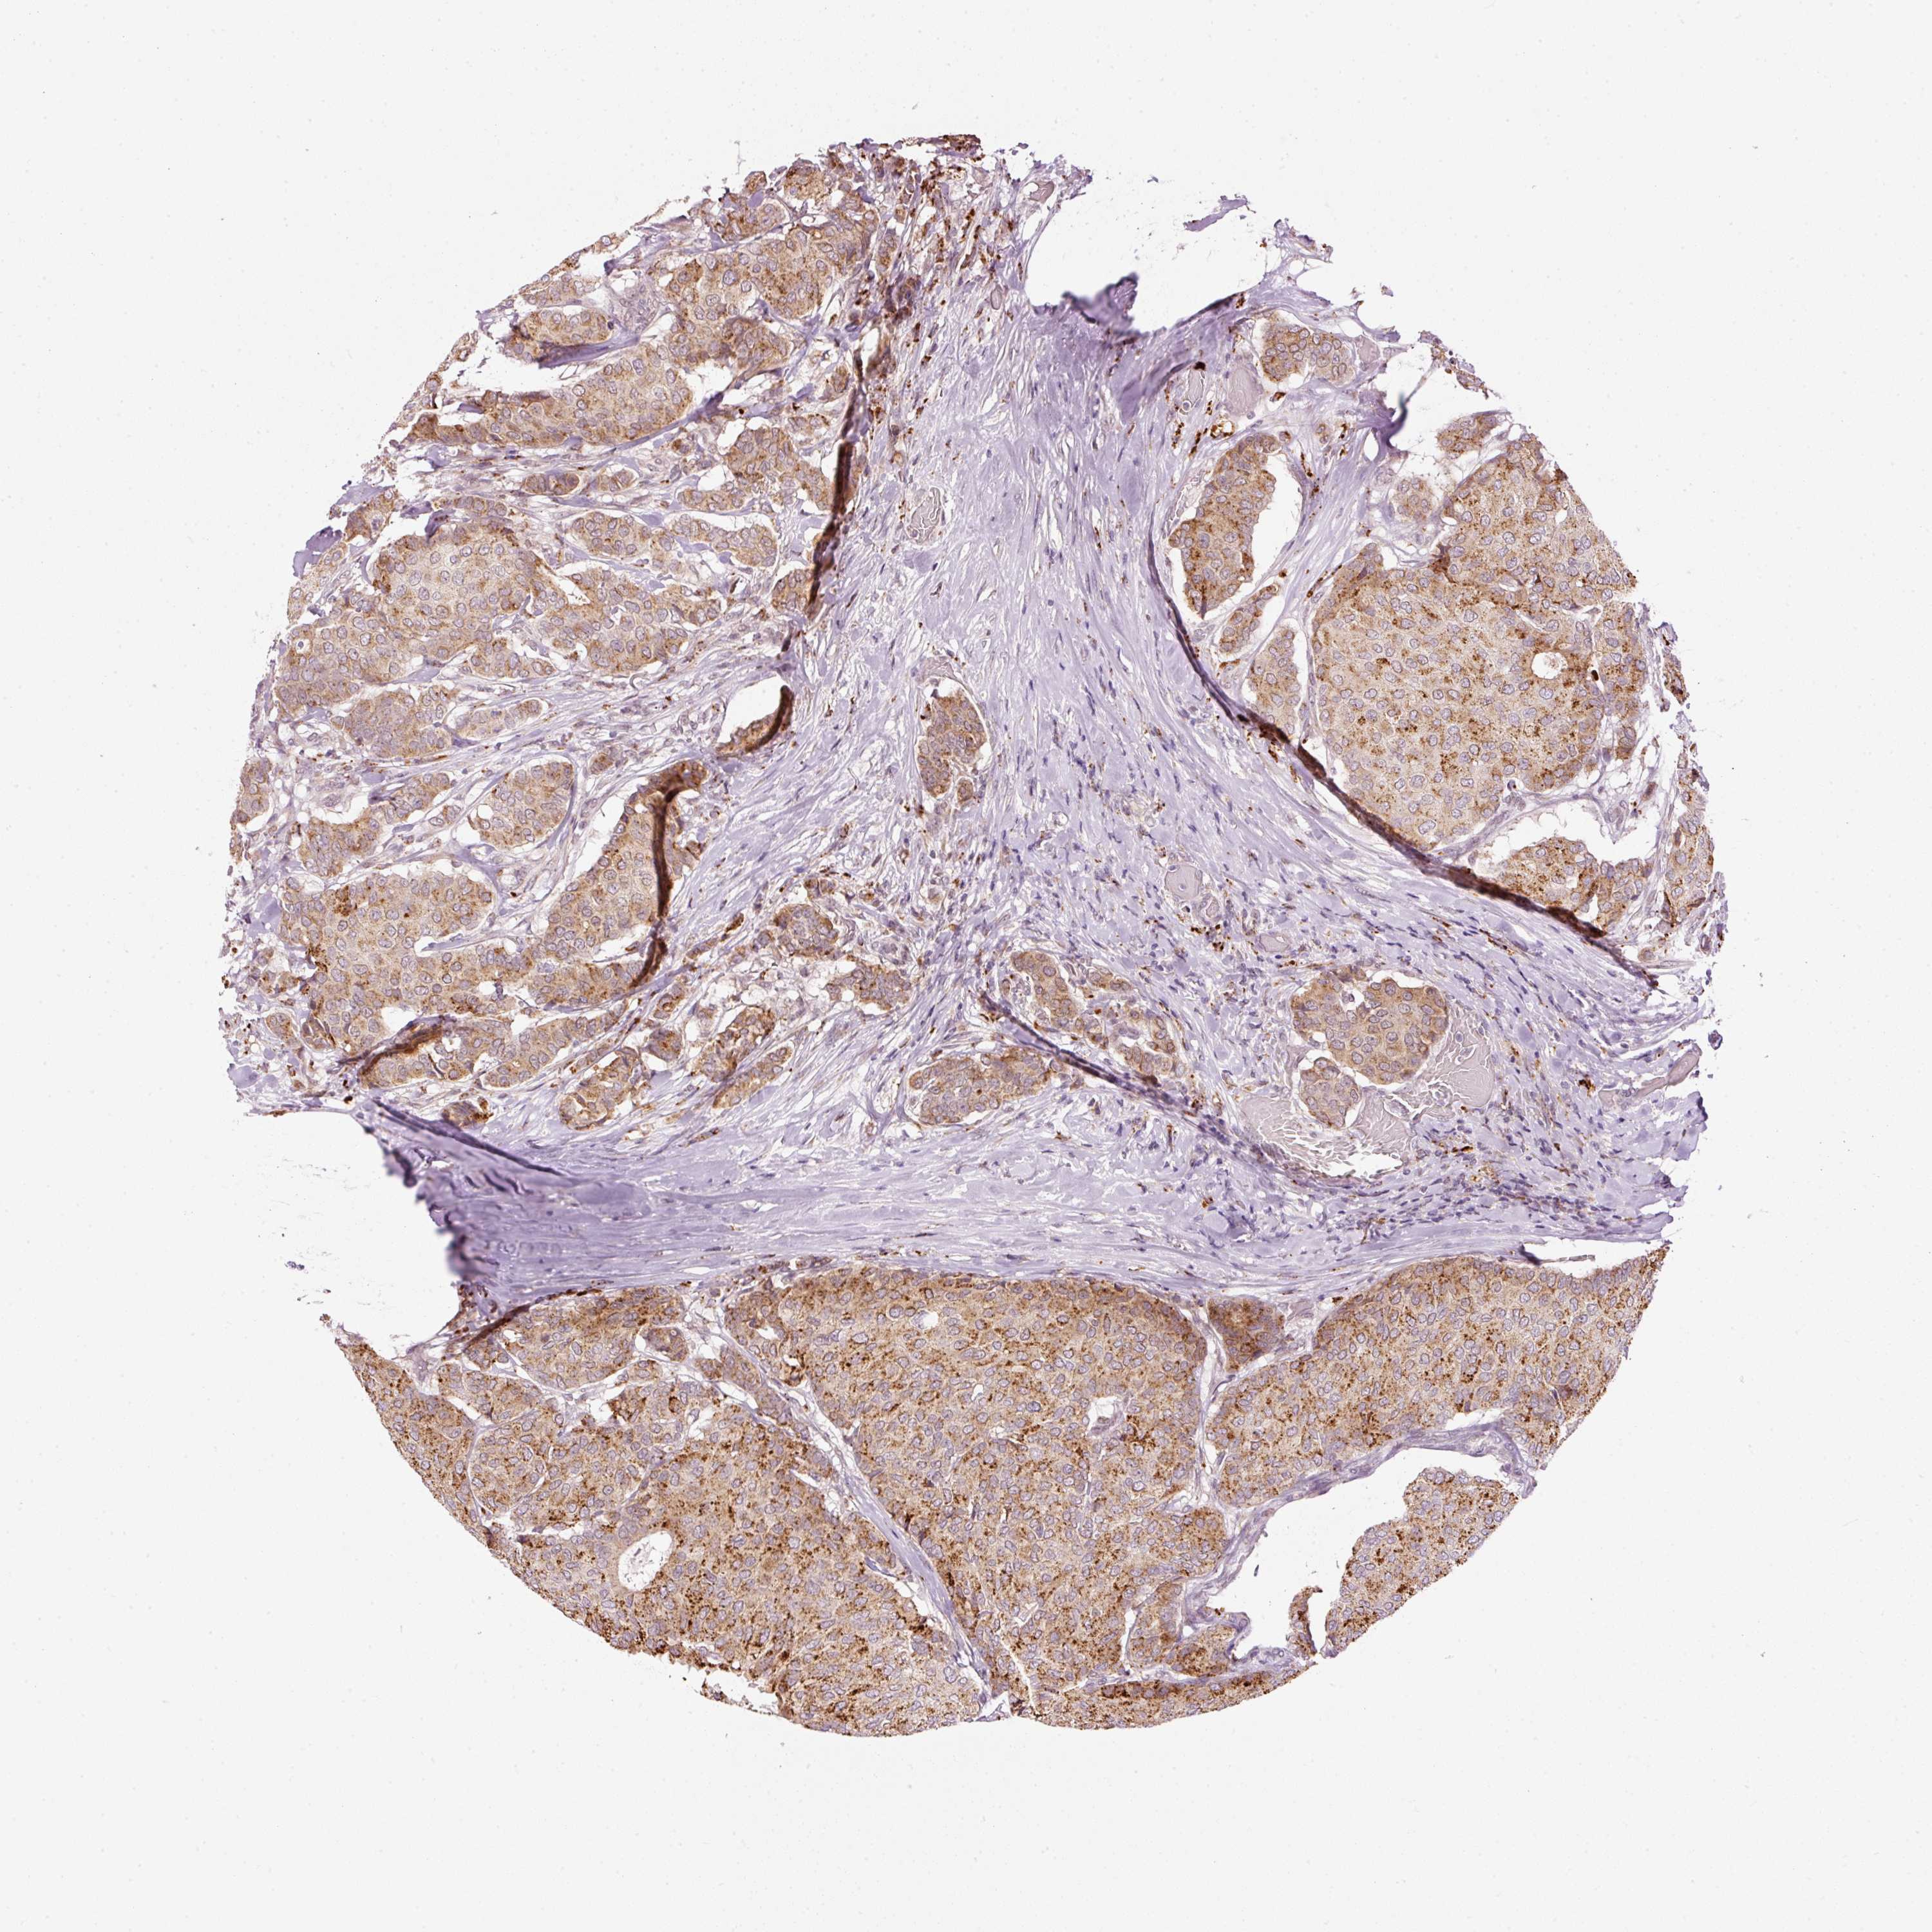

BRCA TCGA BRCA VALIDATION PROTEIN EXPRESSION